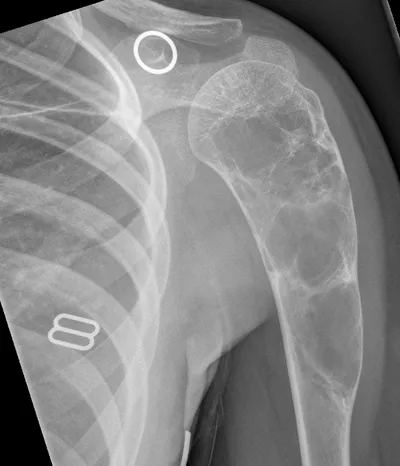

Multiple epiphyseal dysplasia

XRAYPelvisDysplasia+1

4/23/2026